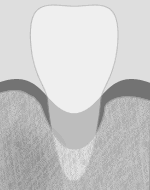

正常

健常な歯周ポケットは、2~3mm です。 治療 3~6カ月に一度、定期検診を行いしっかりとプラークコントロールしましょう。 歯周ポケットが2mm以下でもプラークがついているような場合は危険信号です。